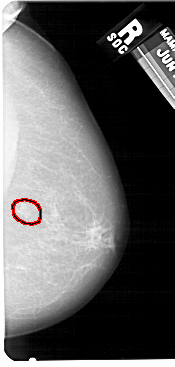

A_1428_1.RIGHT_MLO

RIGHT_MLO LINES 5491 PIXELS_PER_LINE 2836 BITS_PER_PIXEL 12 RESOLUTION 43.5 OVERLAY

FILE: A_1428_1.RIGHT_MLO.OVERLAY

TOTAL_ABNORMALITIES 1

ABNORMALITY 1

LESION_TYPE MASS SHAPE LOBULATED MARGINS ILL_DEFINED

ASSESSMENT 4

SUBTLETY 4

PATHOLOGY BENIGN

TOTAL_OUTLINES 1

BOUNDARY